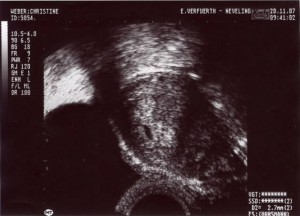

Mama und Papa haben mir freundlicherweise Bilder von meiner Ein-Zimmer-Wohnung zur Verfügung gestellt. Erstellt wurden die mit so einem Ding namens Ultraschall. Ich weiß nur noch, dass ich in den ersten Wochen von dem Teil überhaupt nicht begeistert war und mich immer ganz klein gemacht habe, wenn Mama und Papa schon wieder knippsen wollten. Aber wer lässt sich schon gern freiwillig in seine Privatsphäre schauen?

Hier seht ihr mich als "Würmchen" – eine ganz kleine Bohne.